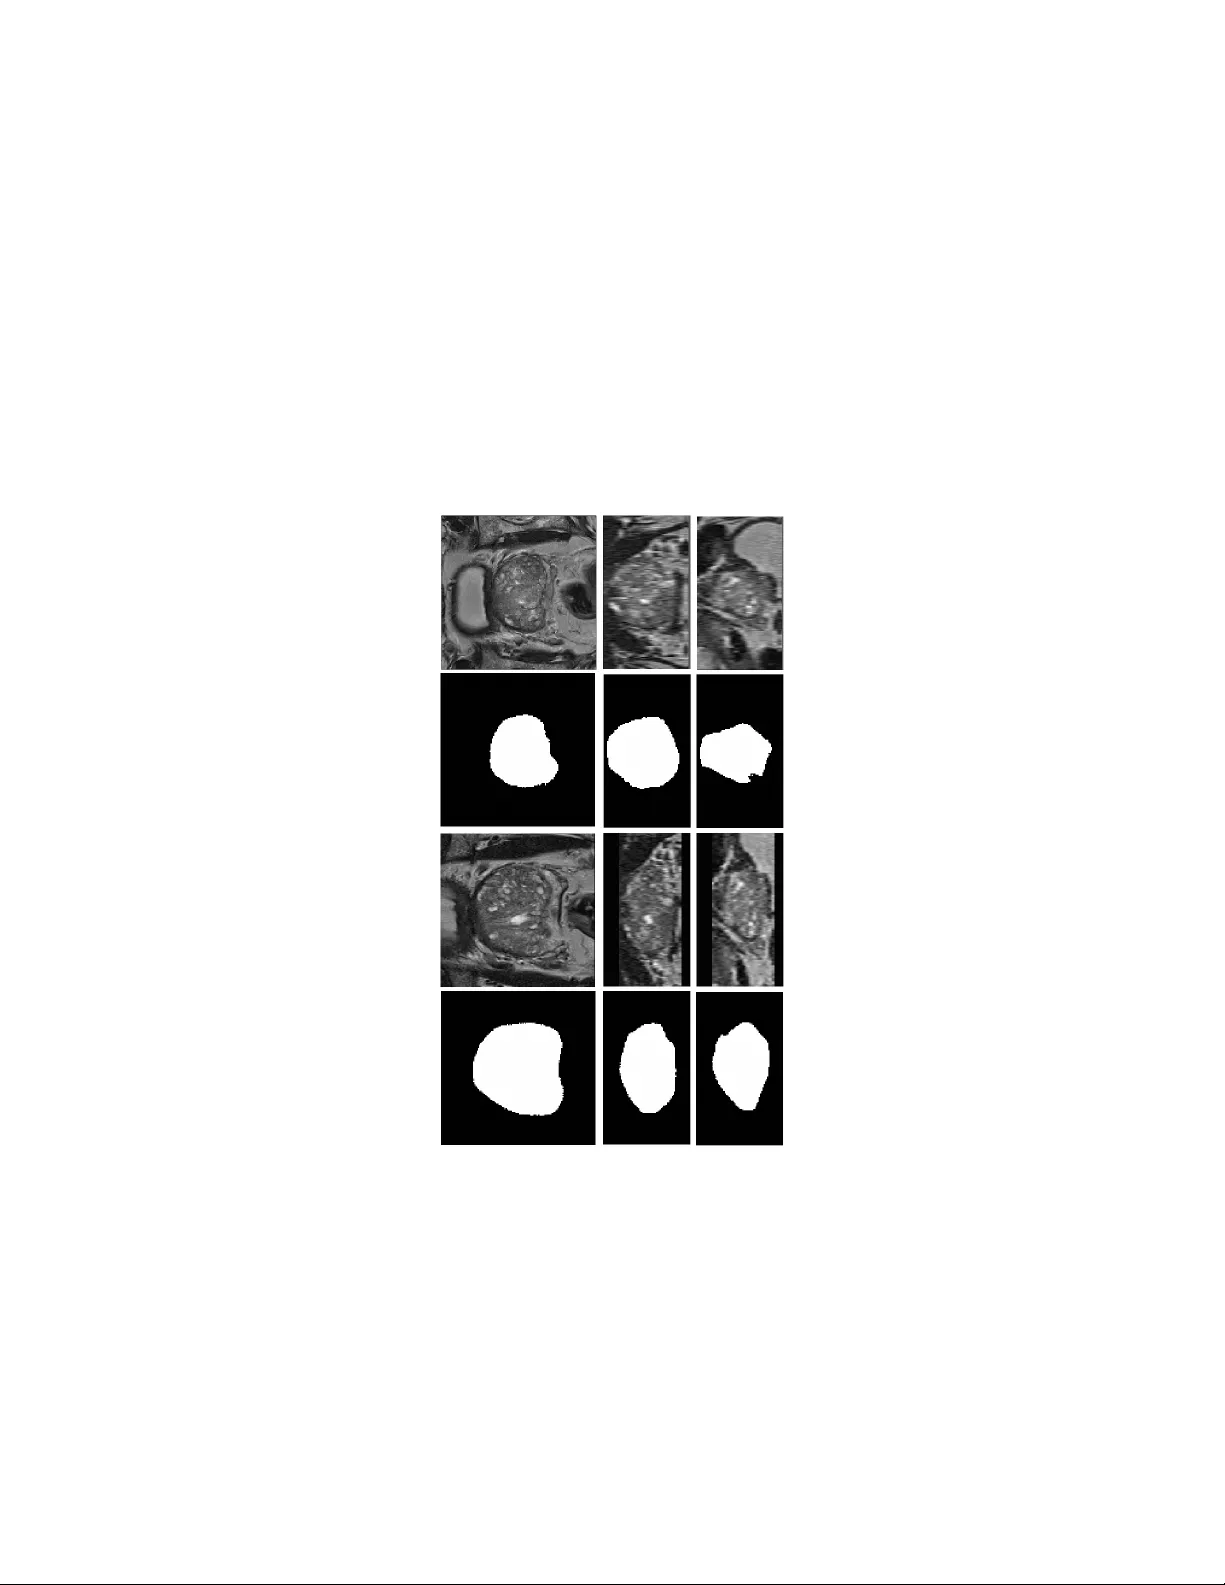

본 연구는 전립선 T2‑가중 MRI에서 자동으로 정확한 분할을 수행하기 위한 새로운 딥러닝 기반 파이프라인을 제안한다. 전립선은 환자마다 형태·크기·조직 대비가 크게 다르고, 라벨링된 학습 데이터는 제한적이기 때문에 기존의 단일 CNN 접근법은 과적합이나 일반화 실패를 겪기 쉽다. 이를 해결하고자 저자들은 두 개의 별도 CNN을 설계하였다. 첫 번째 단계인 전역(Global) CNN은 전체 3D 이미지(128 × 128 × 72 voxel)를 입력받아 전립선에 대한 소프트 마스크를 출력한다. 이 마스크는 전립선의 무게중심과 대략적인 경계를 제공하며, 이후 전립선 형태 모델을 입자 군집 최적화(Particle Swarm Optimization)로 피팅해 외부 잡음이나 이상치를 제거한다. 이렇게 추정된 중심과 크기를 바탕으로 전립선을 포함하는 볼륨 오브 인터레스트(VOI)를 정의하고, 이를 80 × 80 × 48 voxel 크기로 재샘플링한다. 두 번째 단계인 지역(Local) CNN은 재샘플링된 VOI를 입력으로 받아 고해상도 경계 정보를 학습한다. 전역 단계에서 이미 전립선이 이미지 중앙에 고정되고 크기가 표준화되었기 때문에, 지역 CNN은 얕은 네트워크(d = 3)로도 충분히 정밀한 경계 분할을 수행한다. 두 네트워크 모두 인코더‑디코더 구조에 잔차 모듈과 짧은·긴 스킵 연결을 결합한 U‑Net 스타일을 사용한다. 전역 CNN은 깊이 d = 5로 설계해 넓은 수용 영역을 확보하고, 지역 CNN은 얕은 구조로 파라미터 수를 최소화한다. 데이터 전처리 과정에서는 N4ITK를 이용한 바이어스 보정, 1 mm³ 등방성 리샘플링, 중앙 크롭 또는 제로 패딩을 통한 고정 크기(128 × 128 × 72) 확보, 그리고 평균 0·표준편차 1로 정규화한다. 데이터 증강은 전립선 형태 모델을 기반으로 변위장을 생성해 학습 이미지와 라벨을 변형함으로써 실제 임상에서 나타날 수 있는 다양한 형태 변이를 시뮬레이션한다. 무작위 잡음과 변위도 추가해 네트워크가 지역 최소에 빠지는 것을 방지한다. 학습은 PROMISE12 챌린지 데이터셋(50 train / 30 test)을 사용했으며, 5‑fold 교차 검증을 통해 최적 네트워크 크기·학습률·드롭아웃 비율을 탐색하였다. 교차 검증 결과를 바탕으로 최종 모델을 전체 50장의 학습 데이터에 대해 재학습하고, 테스트 이미지 30장에 적용했다. 결과는 평균 Dice 90.6 ± 2.2로, 기존 모든 방법을 능가한다. 정량적 성능 외에도 생성된 마스크는 매끄럽고 인공적인 아티팩트가 거의 없으며, 후처리는 0.5 임계값 적용 후 반경 2 mm 구형 구조 요소를 이용한 오프닝 연산만으로 충분했다. 이 논문의 주요 기여는 다음과 같다. (1) 전역‑지역 이중 CNN 구조를 도입해 제한된 라벨링 데이터에서도 효과적으로 학습할 수 있게 함, (2) 전립선 형태 모델을 활용한 변형 데이터 증강으로 학습 샘플을 인위적으로 확대, (3) 네트워크 깊이를 단계별로 최적화해 파라미터 효율성을 극대화, (4) 간단한 전처리·후처리만으로도 높은 품질의 마스크를 자동 생성. 이러한 설계 원칙은 전립선 외에도 데이터가 부족한 다른 장기·조직의 의료 영상 분할에 적용 가능할 것으로 기대된다. 다만, 형태 모델이 전립선에 특화돼 있어 새로운 장기에 적용하려면 모델 재구축이 필요하고, 전역 CNN에 전체 3D 볼륨을 투입하는 과정에서 메모리 요구량이 비교적 높다는 점은 실용적인 제한 요소이다.